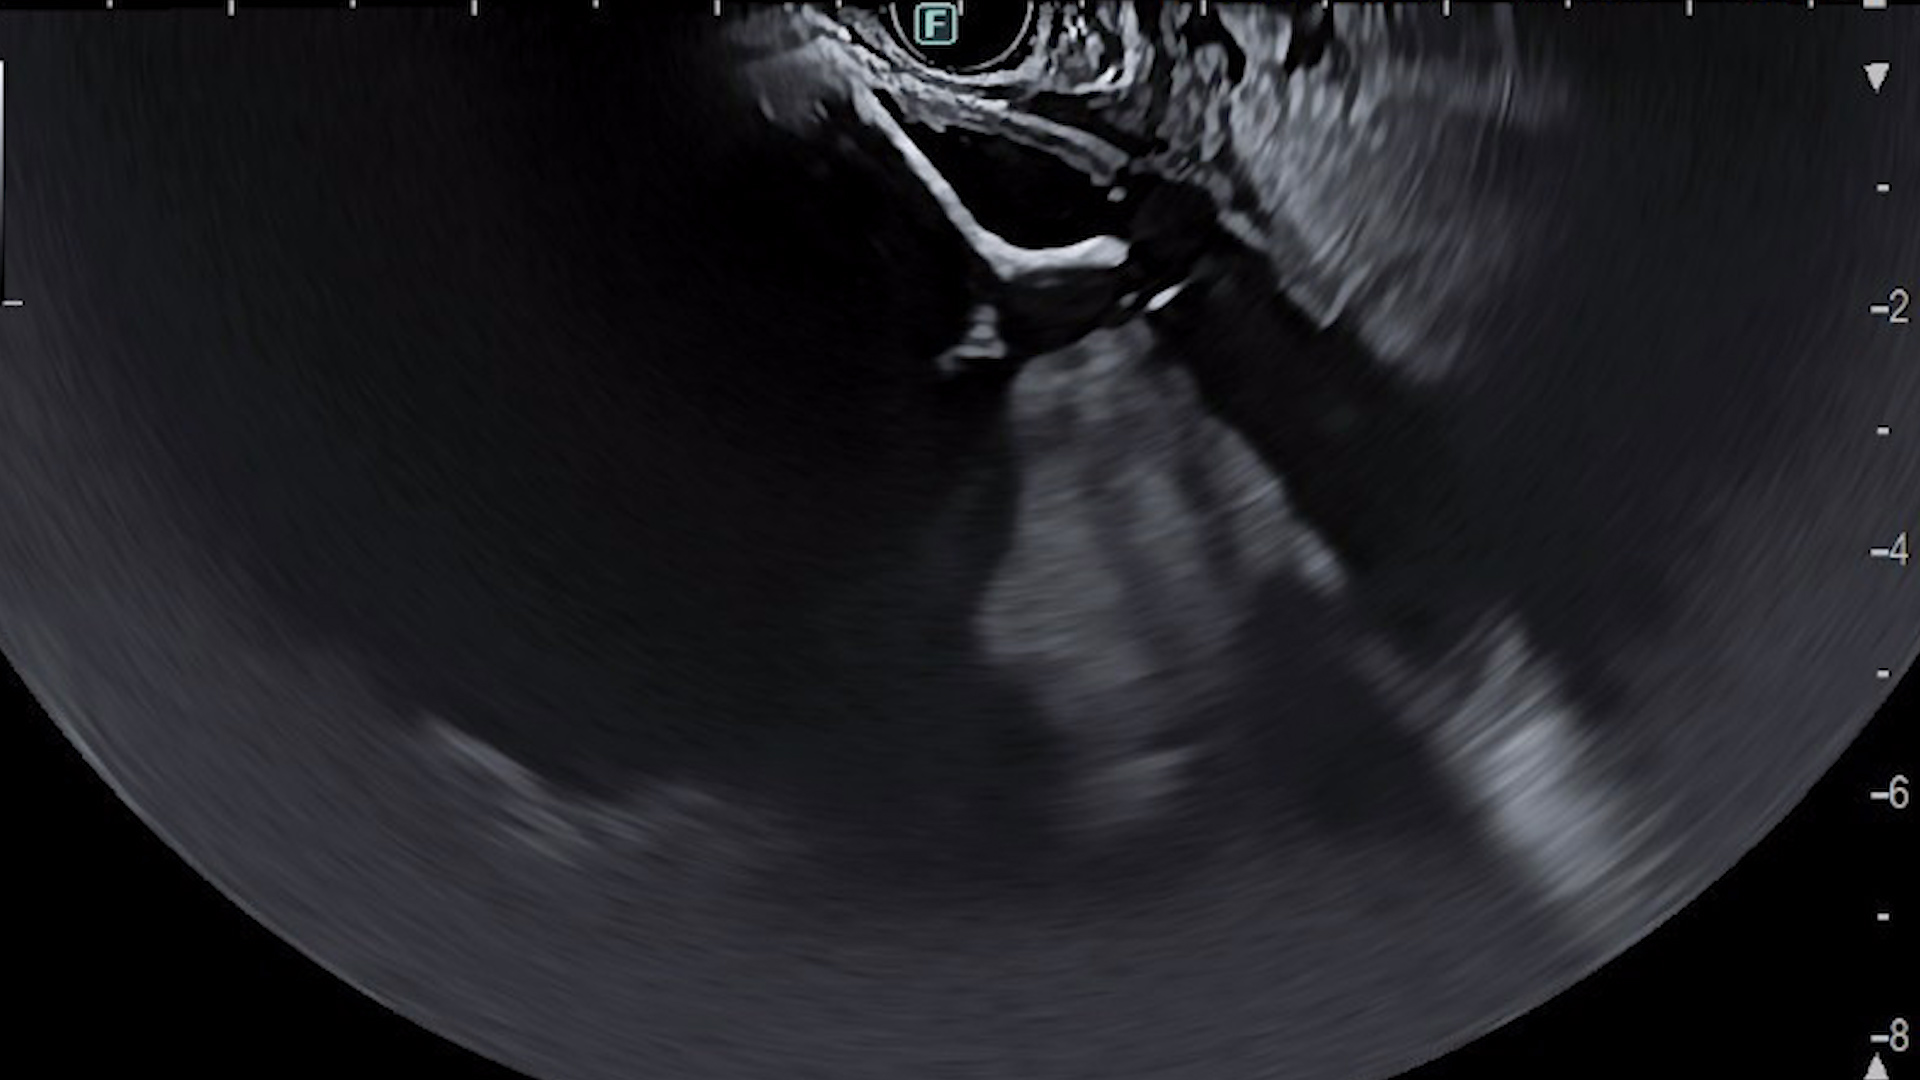

Drenajul ecoendoscopic:

Examinarea ecoendoscopică evidențiază colecție peripancreatică de mari dimensiuni (12/7/6 cm) cu zone hiperecogene declive, cu aspect sugestiv pentru necroză (Film 1). S-a efectuat puncție ghidată EUS cu ac FNA 19G și s-a aspirat lichid brun. Ulterior, sub ghidaj EUS și ghidaj radiologic, s-a montat transgastric stent tip LAMS (HotAXIOS, Boston Scientific) 15 mm pe fir ghid 0,035 Fr, cu drenajul a cca. 1000 mL lichid brun (Fig. 3-4). Ulterior s-a introdus un stent dublu pigtail prin stentul metalic LAMS (Fig. 5).